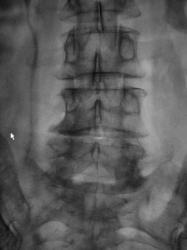

Пол пациента: Мужской пол Тип патологии: Другое Область исследования: Мочеполовая система Методы исследования: Rg Пациент направлен в рентгеновский кабинет для производства внутривенной урографии с подозрением на опухоль левой почки. Произведено стандартное исследование. Ваше мнение коллеги? Вс, 24/05/2009 - 21:05 #1 Андрей Юрьевич Не на сайте Был на сайте: 1 неделя 4 дня назад Зарегистрирован: 16.11.2008 - 22:16 Публикации: 18098 Такой можно и коралловидным назвать. Андрей Юрьевич Пнд, 25/05/2009 - 10:47 #2 v1tal Не на сайте Был на сайте: 4 года 9 месяцев назад Зарегистрирован: 07.06.2008 - 19:41 Публикации: 1779 А сколько лет пациенту? В анамнезе туберкулеза нет? "Знаешь, у некоторых врачей есть комплекс мессии — им необходимо спасать мир. А у тебя комплекс Рубика — тебе необходимо решать головоломки." Пнд, 25/05/2009 - 15:45 #3 Катенёв Валенти... Не на сайте Был на сайте: 7 лет 3 недели назад Зарегистрирован: 22.03.2008 - 22:15 Публикации: 54876 В анамнезе туберкулёза (легочного) нет. Пациенту 42 года. Мочу, сейчас, у всех пациентов с "урологической патологией" на МБТ и "смотрят и сеют". А какое мнение коллег по поводу правой почки?

В анамнезе туберкулёза (легочного) нет. Пациенту 42 года. Мочу, сейчас, у всех пациентов с "урологической патологией" на МБТ и "смотрят и сеют".

А какое мнение коллег по поводу правой почки?